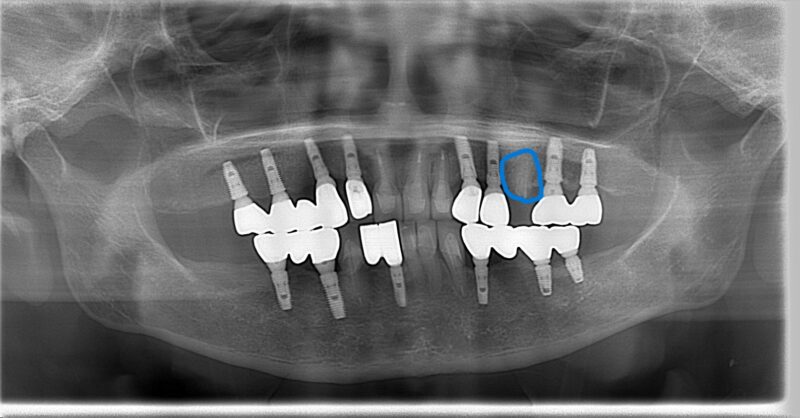

*術前写真 青いマークが抜歯

診断の結果、問題となった左上の失活歯(神経が死んでしまった歯)は抜歯が必要でした。通常であれば、この歯を失うことで大きな問題になりそうですが、幸いなことに両サイドにインプラントが入っていたのです。

- 問題のある天然歯を抜歯

- 両サイドのインプラントを支台として活用

- インプラント上部構造のみを作り直し